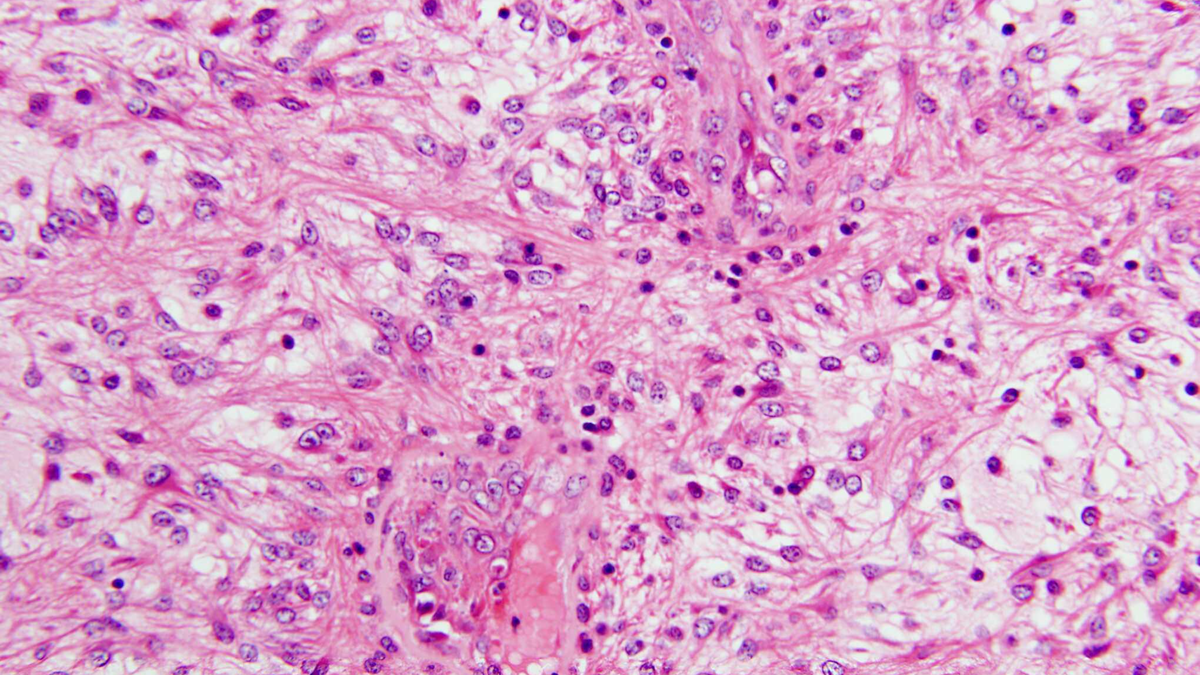

Белое вещество долго воспринималось как «кабельная система» мозга - пучки аксонов, передающих сигналы между областями. Однако исследования, проведённые в ведущих нейробиологических центрах Европы и США, показали: в белом веществе присутствует особая популяция астроцитов, обладающих способностью к пролиферации, то есть делению.

В отличие от зрелых астроцитов серого вещества, эти клетки сохраняют частично «молодой» профиль. Они могут:

· делиться во взрослом мозге,

· мигрировать в соседние зоны,

· менять свою функцию в зависимости от среды.

Фактически белое вещество оказалось не просто проводником сигналов, а динамическим клеточным резервом.